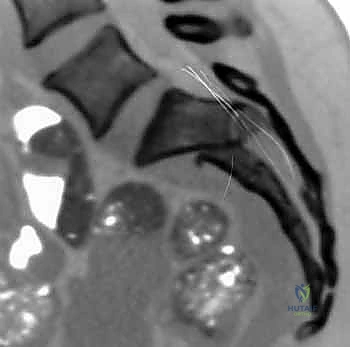

* المسامير الطبية (Screws): تُثبت الشرائح بالعظم، وتُستخدم أحياناً مسامير طويلة (Iliosacral Screws) لربط عظم الحرقفة بالعجز لضمان استقرار المفصل.

يتم الاستعانة بجهاز الأشعة السينية المتحرك داخل غرفة العمليات (C-arm Fluoroscopy) للتأكد من وضعية المسامير بدقة المليمتر، لضمان عدم اختراقها للأعصاب أو الأوعية الدموية.